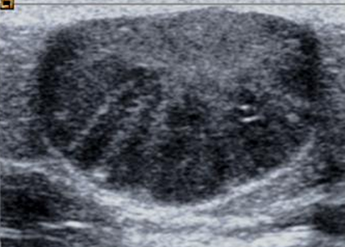

Fig 217 A. Quiste sebáceo.

Ecografía. Imagen ovalada, superficial y bien definida, con ecos internos. Produce reforzamiento posterior, lo que indica su composición líquida.